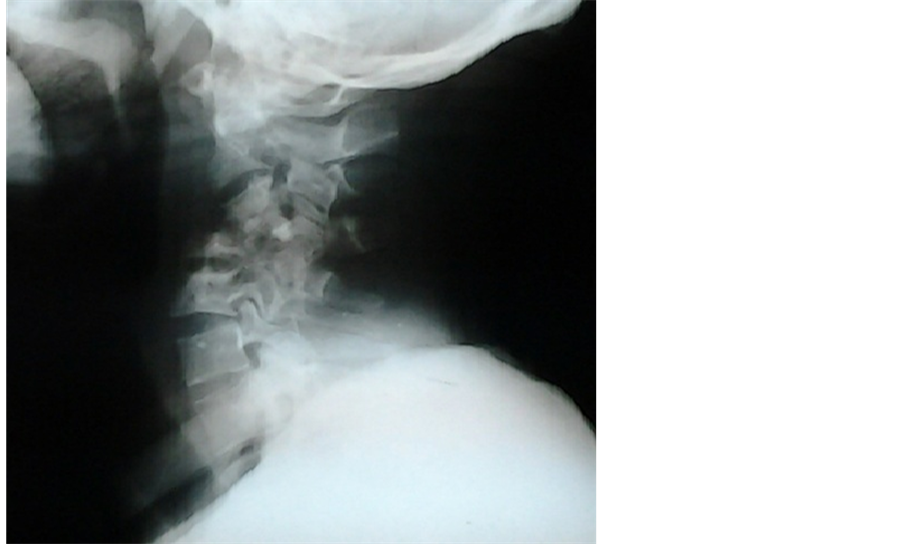

His full blood count, electrolytes, urea and creatinine were within normal limits. His erythrocyte sedimentation rate was 40 mm/hr using the Westergren method. Plain cervical spine X-ray (Figure 1) showed destruction of C3 to C5 vertebral bodies and their intervening discs as well as segmental kyphosis. A Magnetic Resonance Imaging scan of his cervical spine (Figure 2) further showed a retropharyngeal prevertebral abscess.

Figure 1. Plain cervical spine X-ray of the patient showing collapsed vertebral bodies of C3 to C5 with destruction of their intervening discs, and segmental kyphosis.